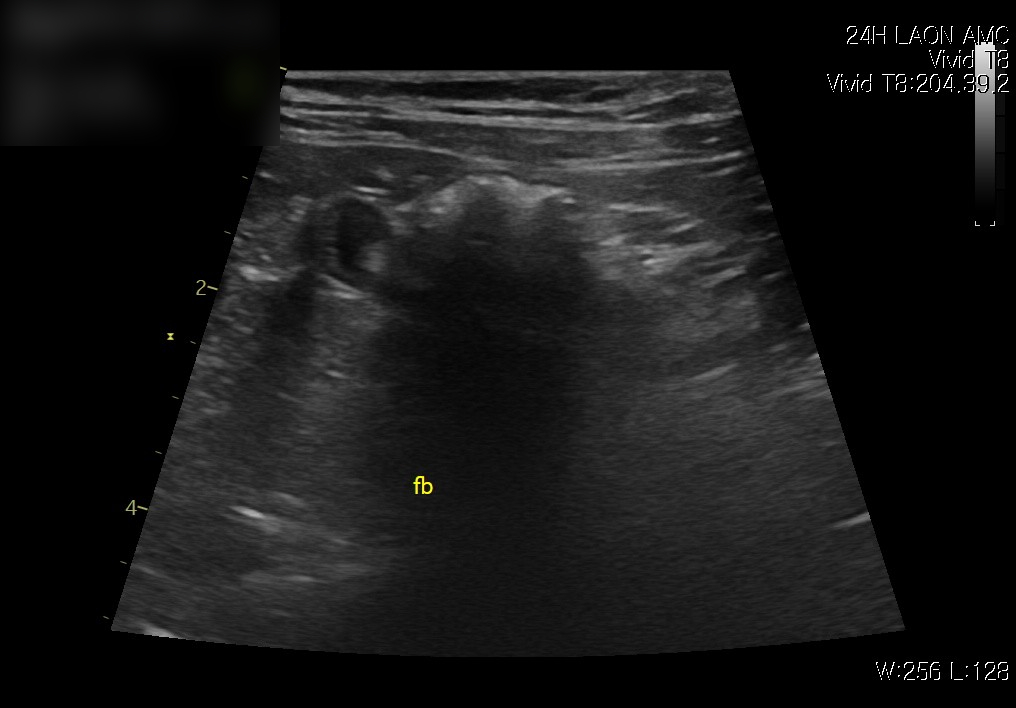

복부초음파 검사 결과

위내액체저류 확인(좌) / 이물확인(우) / 출처: 라온동물메디컬센터

초음파 검사에서 장 내에 이물 의심 소견이 확인되었고, 이물로 인해 위 내 음식물이 내려가지 못하고 저류된 상태가 관찰되었습니다.